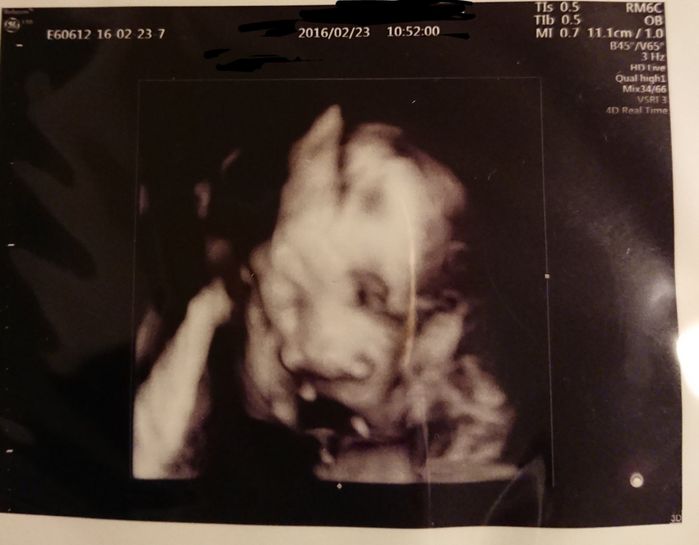

妊娠26週目 性別判明!赤ちゃんの名前が舞い降りた!

前回わからなかった性別がやっとわかりました。ドキドキして待っていると、先生が「女の子だよ! おしゃぶりの練習をしているのかな?」と。このエコー写真を見た時、突然ビビビッと感じ「メイ」と名付けようと決めました。